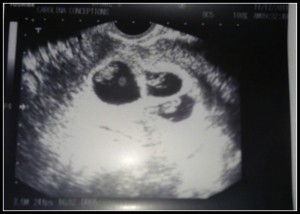

How far along? Eight weeks Saturday so 8w2d today.

Genders? {I updated it to Genders!} We hope & pray for healthy babies first & foremost. But I’d love to have boy/girl combos.

Milestones? My former blueberries are now lentil beans with hands & feet with webbed fingers & toes & eyelids!